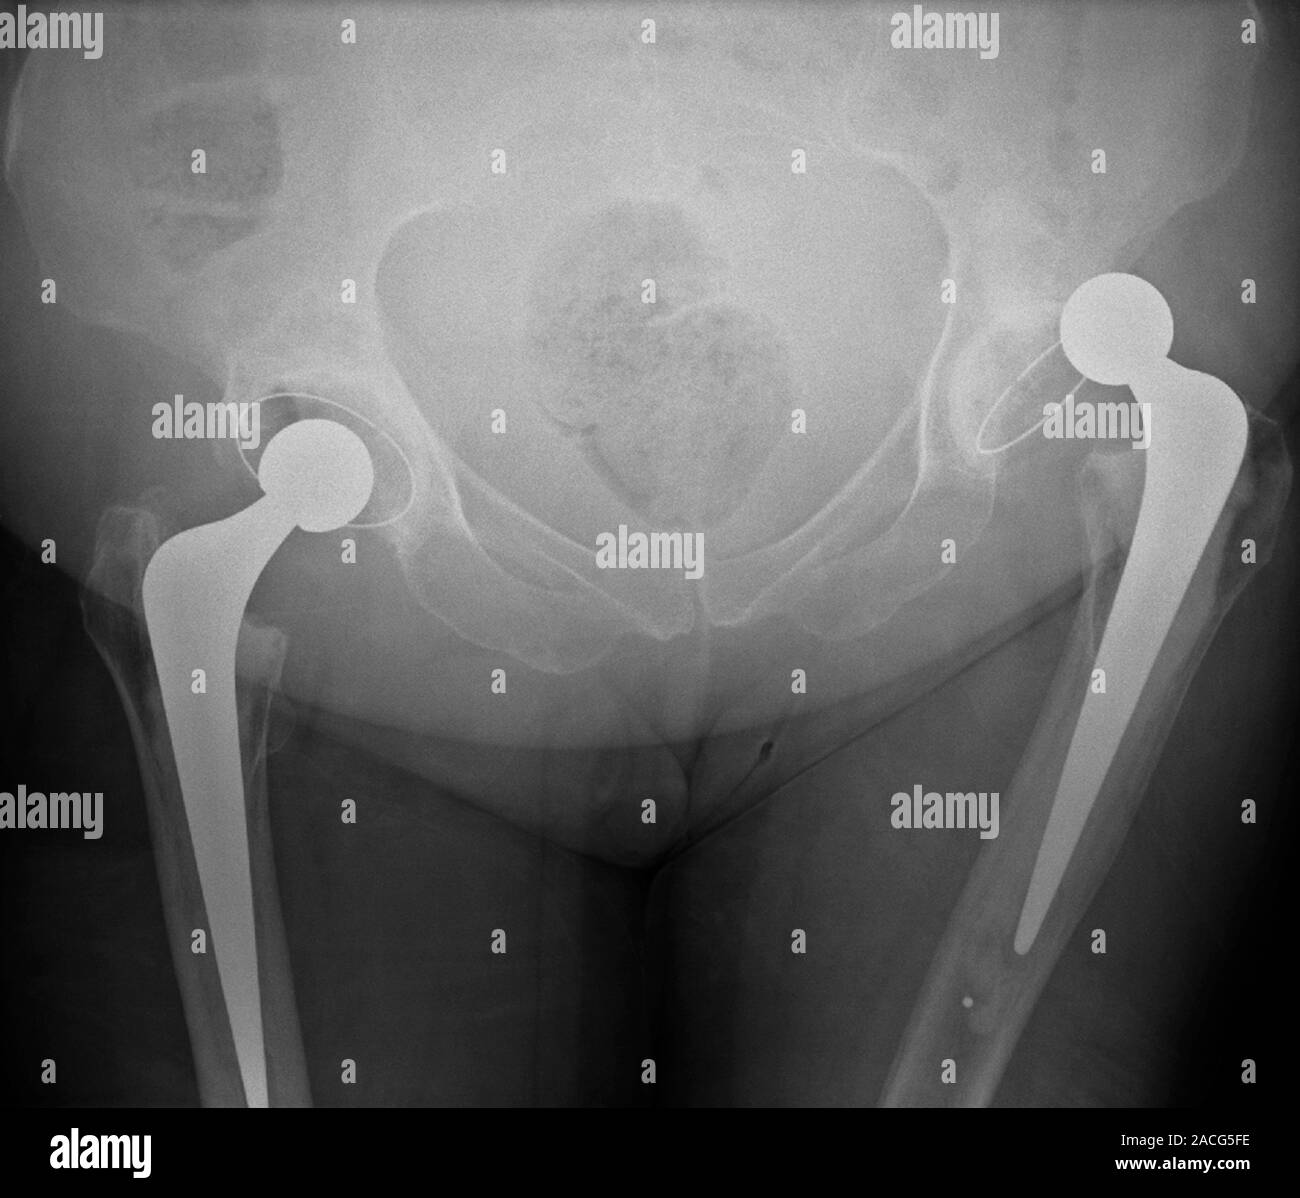

Dislocated hip replacement. Frontal Xray of the pelvis of a patient Total Hip Replacement Dislocation Treatment Treatment of instability after total hip replacement should follow a standardized algorithm. The risk of dislocation after primary. Surgical management with possible revision tha is indicated for irreducible dislocations, recurrent instability, and implant. After a total hip replacement, you will be able to resume most activities. But if you have a replacement hip, it may have dislocated more easily, from. Total Hip Replacement Dislocation Treatment.